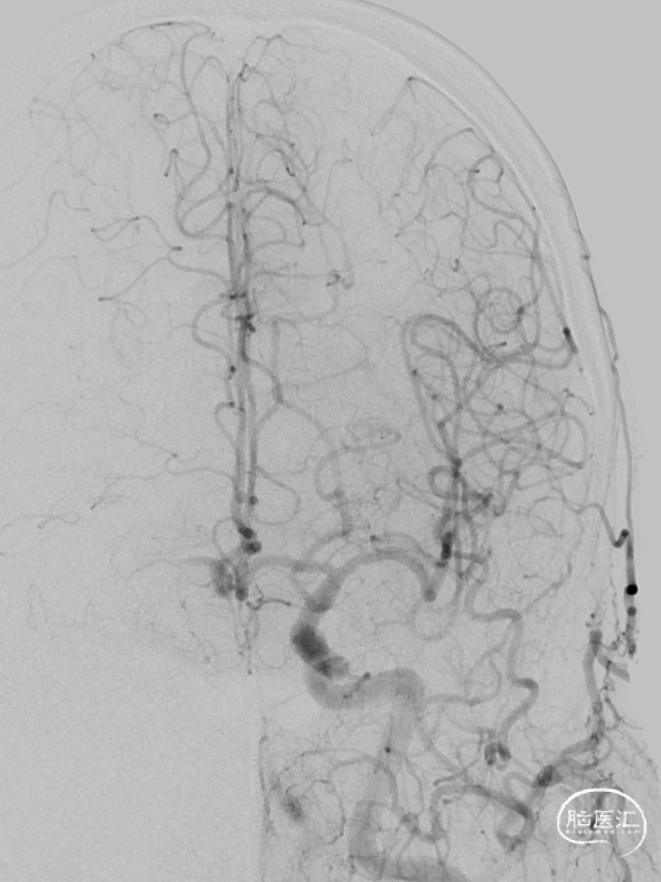

将Synchro(0.014×300cm)微导丝外衬Gateway(2.0×15mm)球囊缓慢通过RMCA M1段狭窄处,球囊定位于RMCA狭窄处缓慢扩张,压力6atm。采用交换技术置入灌注微导管,并将4.0×16mm支架定位于狭窄处释放。

复查造影见支架展开良好,支架内及远端血流通畅,TICI分级3级。术顺,术毕,Proglide缝合术口。

术后第一天复查颅脑CT未见异常染色及大面低密度病灶。

查头颅MRI:右侧基底节区、右侧顶颞岛叶急性脑梗死。